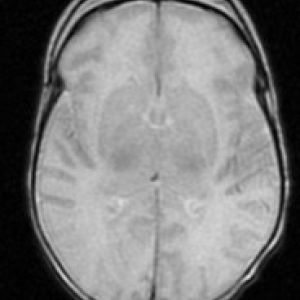

EL EXAMEN NEUROLÓGICO EN EL NEONATO

El examen neurológico (EN) es una herramienta clínica que nos permite aproximarnos a la evaluación funcional del sistema nervioso y tiene un enorme valor para establecer la naturaleza y localización de déficits funcionales del sistema nervioso central (SNC) y periférico (SNP).